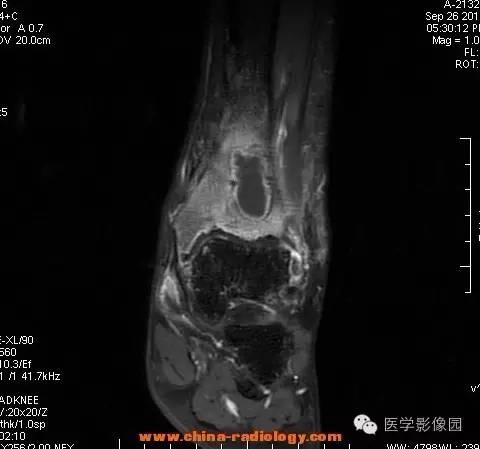

【病例】胫骨骨脓肿1例MR影像表现

影像学表现:胫骨中下段干骺端不未规则形长T1长T2信号,T2WI见不完整环形稍低信号影,T2脂肪抑制低信号更明显,并见胫骨下段及踝关节后外侧软组织呈弥漫稍高信号,增强明显不均匀强化,增强见低信号环内有环形强化影。

影像学表现:表现为长骨干骺端有椭圆形密度减低区,边缘有清晰的骨质硬化,病变与邻近正常骨髓腔境界清楚。MRI上T1WI呈低信号,少数呈等信号,T2WI多为混杂高信号,增强扫描可见环状强化,强化的脓肿壁薄而均匀。